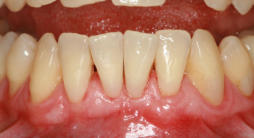

Mikrochirurgischer Wundverschluss

Gingivatransplantat fixiert

Zustand 3 Wochen post OP